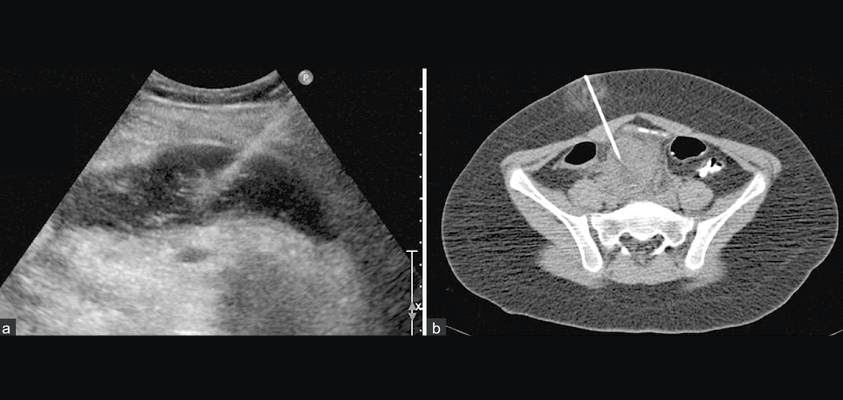

USG (Ultrasound) and CT (Computed Tomography)-Guided procedures are image-guided techniques that allow for accurate diagnosis and targeted interventions with minimal risk and faster recovery.

These procedures are performed using real-time imaging to guide a needle or instrument precisely to the area of concern — such as a cyst, tumor, fluid collection, or abscess — without the need for open surgery.